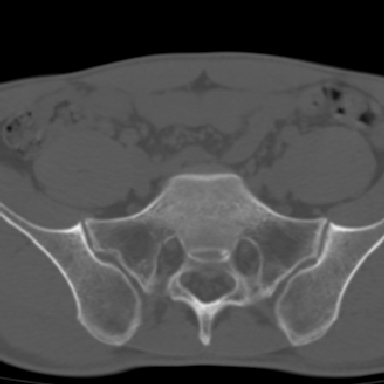

m 30 腰背部不适半年; 清晨时僵硬; 活动症状有所改善

双侧骶髂关节下2/3关节面模糊,毛糙,可见小囊状骨质破坏区.支持强直性脊柱炎.

双侧骶髂关节下2/3关节面模糊,毛糙,髂骨侧可见小囊状骨质破坏区,骶髂关节间隙增宽(软骨破坏期)。支持早期强直性脊柱炎。

双侧骶髂关节下2/3关节面模糊、毛糙,可见小囊状骨质破坏区,呈虫咬状改变,周围可见增生硬化.支持强直性脊柱炎早期表现.

双侧骶髂关节髂骨面硬化,毛糙,小囊变,属于早期强直性脊柱炎